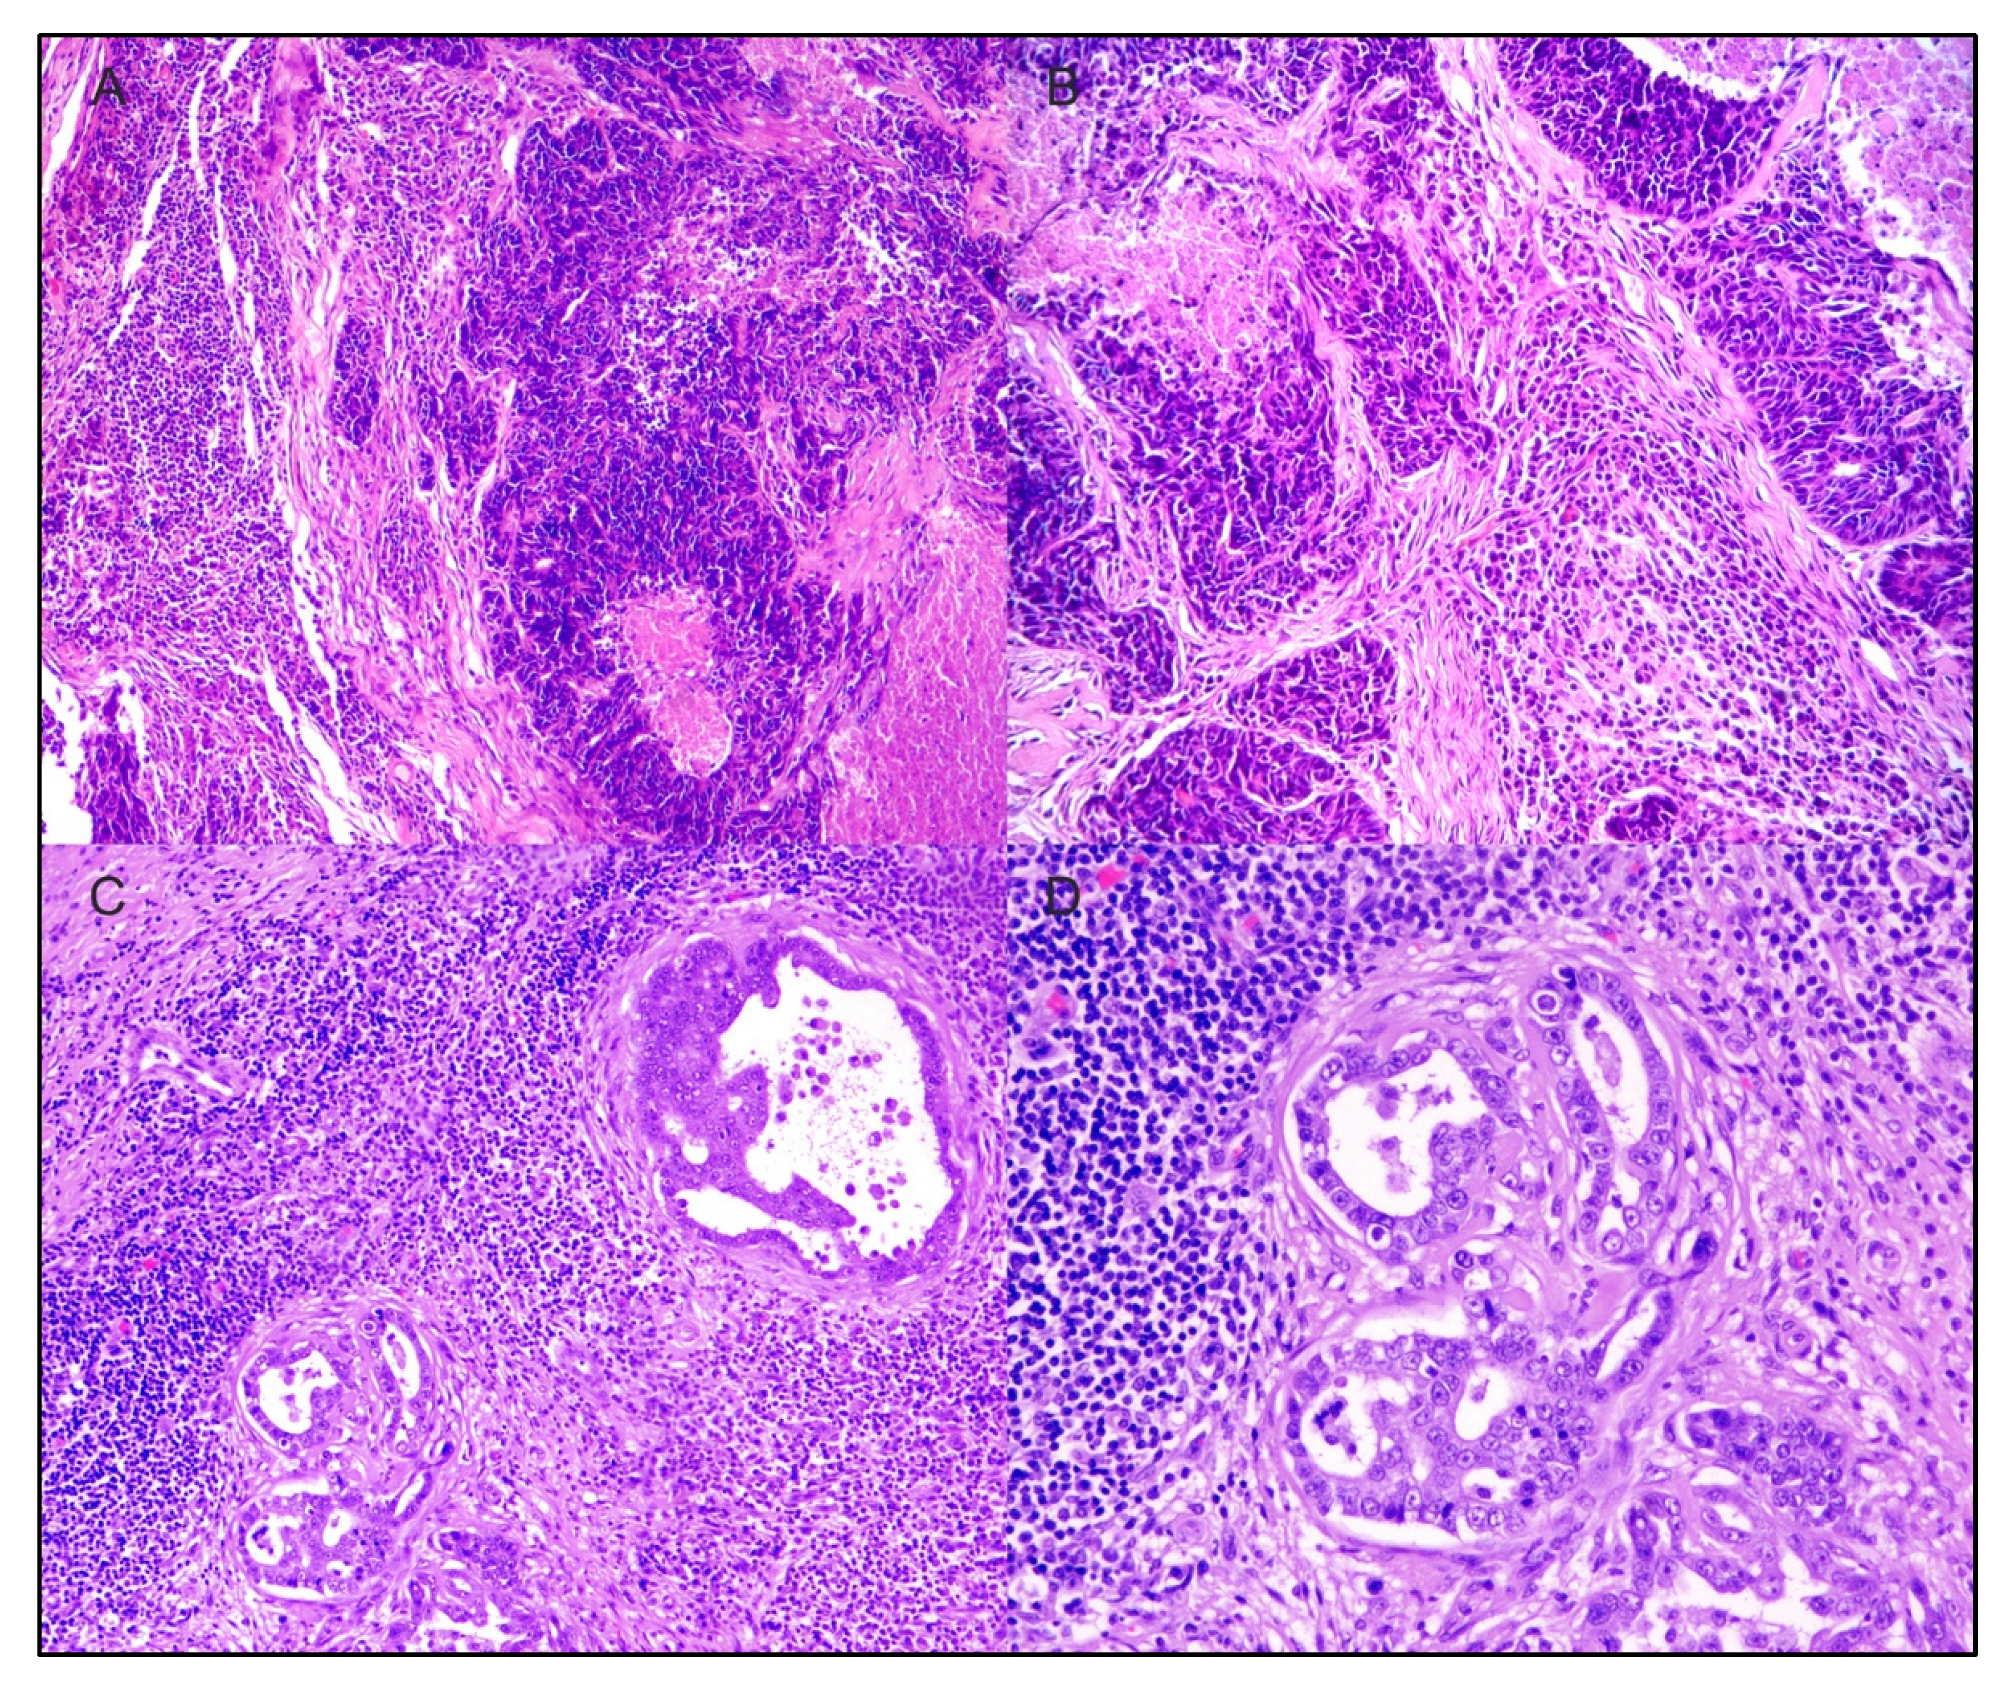

- Lenz, J.A.; Assenmacher, C.-A.; Costa, V.; Louka, K.; Rau, S.; Keuler, N.S.; Zhang, P.J.; Maki, R.G.; Durham, A.C.; Radaelli, E.; et al. Increased Tumor-Infiltrating Lymphocyte Density Is Associated with Favorable Outcomes in a Comparative Study of Canine Histiocytic Sarcoma. Cancer Immunol. Immunother. 2021, 71, 807–818. [Google Scholar] [CrossRef] [PubMed]